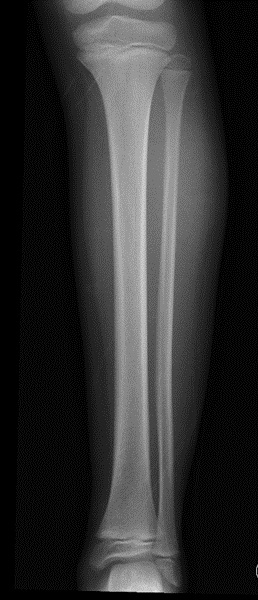

Tras ello, se hizo una ecografía de partes blandas, en la que se observó una colección que medía 7 × 4 × 0,6 cm (Fig. 2) de diámetro con varias loculaciones y ecos en su interior, localizada en la unión entre la fascia y el tejido celular subcutáneo.

| Figura 2. Ecografía de partes blandas. Región pretibial de la pierna izquierda donde se identifica una colección que mide 7 × 4 × 0,6 cm de diámetro, con varias loculaciones y ecos en su interior, localizada en la unión entre la fascia y el tejido celular subcutáneo |

Los hallazgos ecográficos junto con el antecedente traumático directo eran sugerentes de un seroma de Morel-Lavallée.